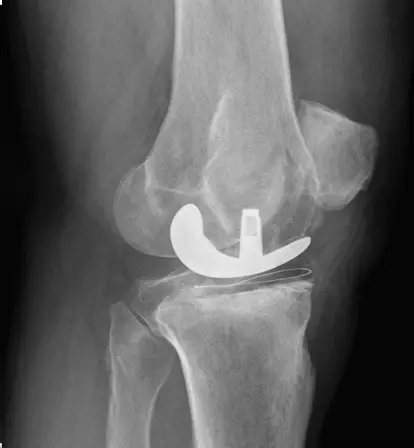

TKR surgery involves removing the damaged knee joint surfaces and replacing them with artificial implants that mimic natural movement. Robotic assistance may be used for precise implant alignment, enhancing joint stability and function.

• Accurate implant alignment with robotic assistance

• Restoration of knee stability and function